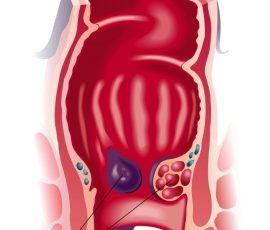

Haemorrhoidal diseases

How do haemorrhoids occur? (Factors)

Increased pressure in the rectum – Chronic diarrhea – Difficult bowel movement or constipation – Holding back the stool – Insufficient physical activity – Not drinking enough water – Overweight – Pregnancy – Regularly eating food low in fibre – Genetic predisposition – Old age

Symptoms of haemorrhoids:

Bleeding – Itching and/or burning – Pain during defecation – Painful feeling in the anus – Swelling in or around the anus – Loss of fluid or mucus

Treatment of haemorrhoids:

Haemorrhoids without symptoms generally does not require treatment. If, however, they protrude from the anus during defecation, cause pain and/or bleeding, medical intervention may be necessary. Several treatments are available, depending on the haemeorrhoid location and severity.